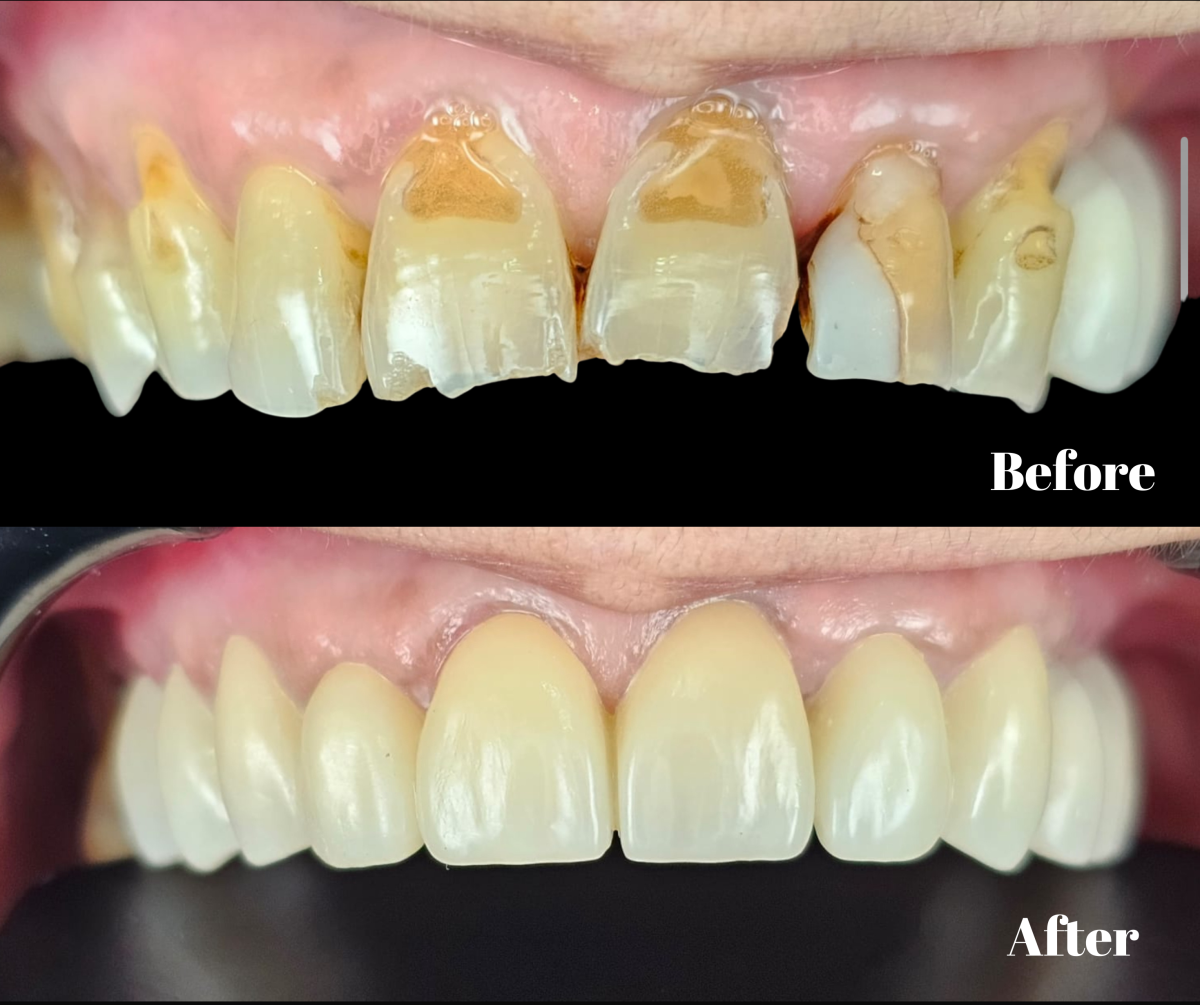

Restaurări indirecte pe suport de zirconiu

Restaurări indirecte metalo-ceramice integral fizionomice